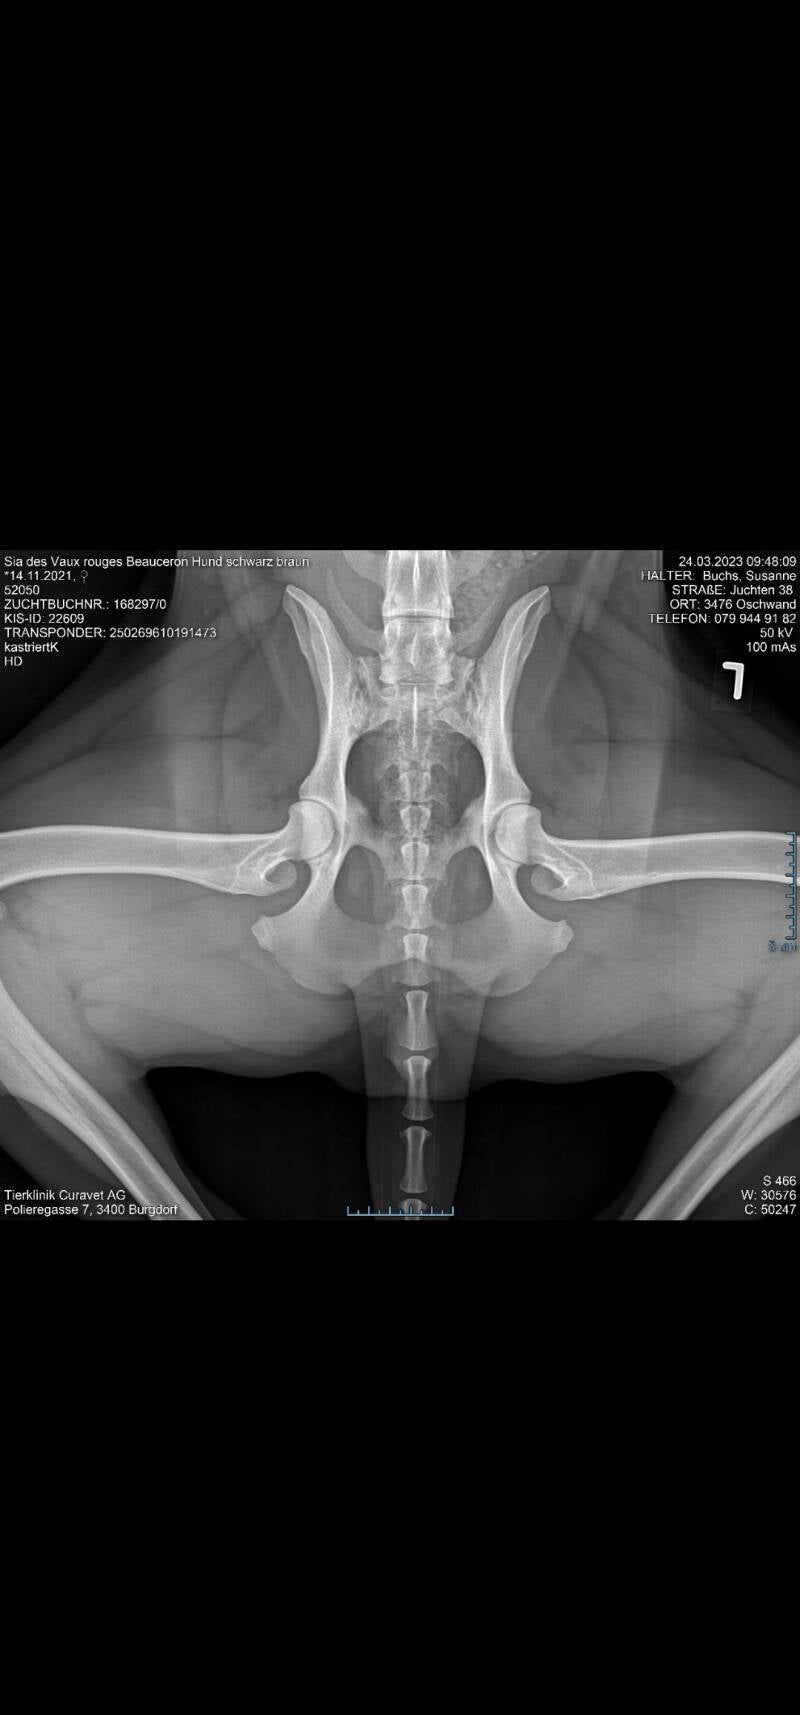

HD: A/A